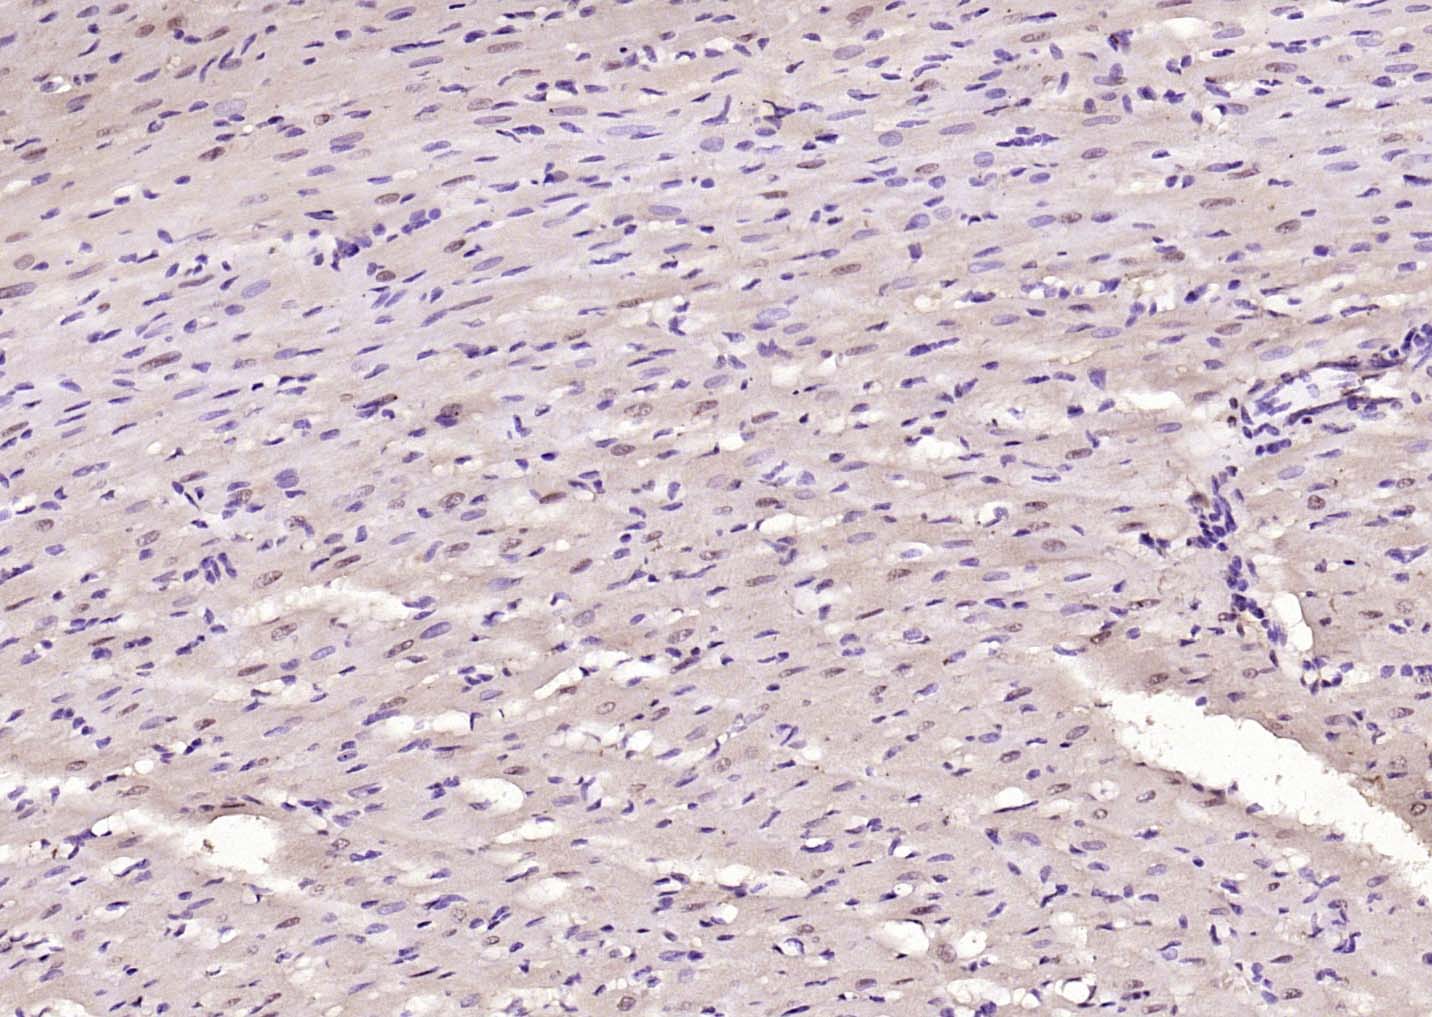

| IHC-P | Human, Mouse, Rat | Cow, Dog, Horse | 1:100-500 |